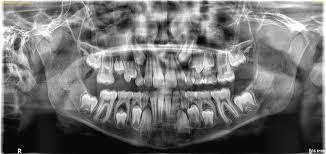

Dental OPG in Nairobi Panoramic Dental X-Ray for Clear, Accurate Oral Diagnosis

Safe, fast, and affordable Dental OPG services in Nairobi using the latest Kodak Carestream technology.

High-Resolution Panoramic Imaging

Full-mouth scans in one quick procedure.

Accurate Diagnosis

Helps detect wisdom teeth, jaw problems, tooth growth, and dental abnormalities.